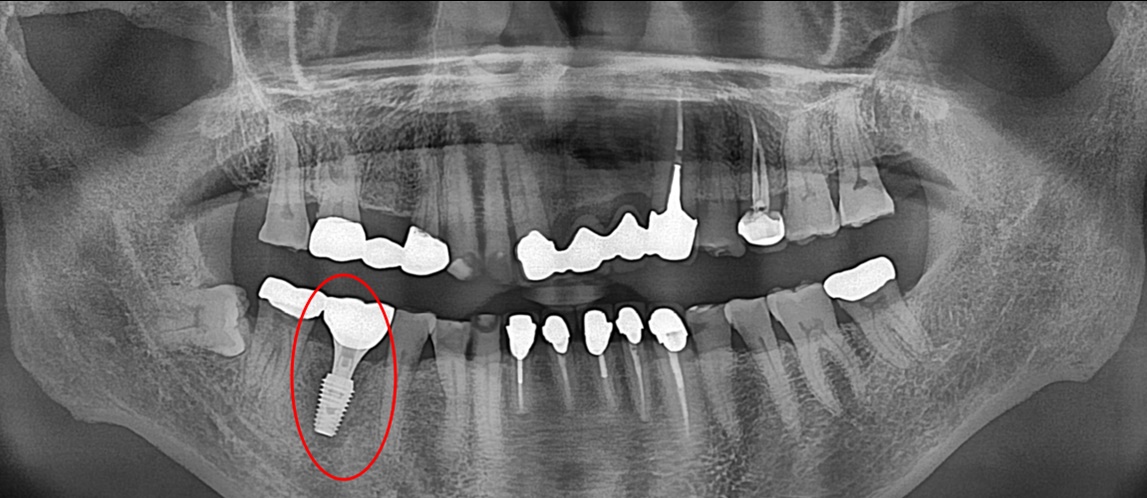

임플란트 식립

발치 부위 이식된 인공 뼈가 단단해진 후 임플란트 식립을 진행하였습니다.

임플란트 치료 완료